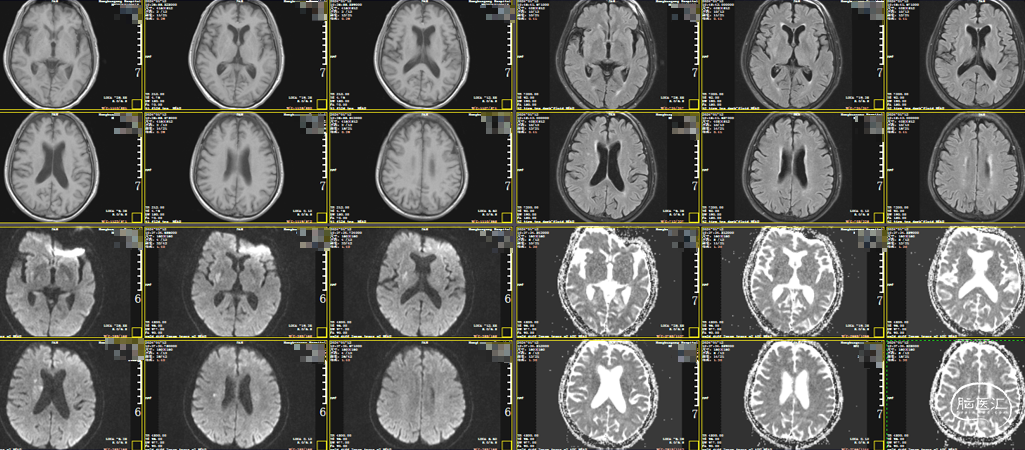

头颅MRI:右侧岛叶、基底节区、放射冠散在急性脑梗死。